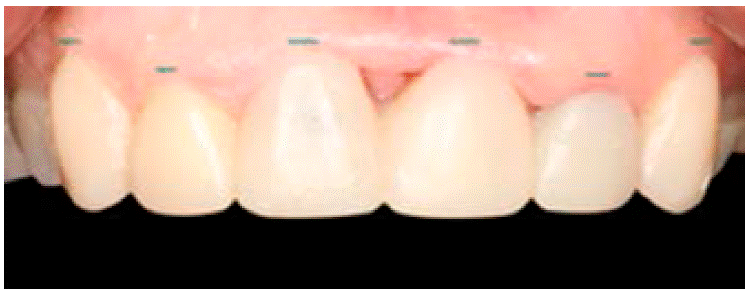

Se realiza el mock up, el cual nos ayudará a ver los alcances que se pueden lograr en el tratamiento (Figuras 4y5).

Una vez colocado el mock up y aceptado por la paciente, se individualiza la zona de los implantes 1.1, 2.1 para comenzar a manipular los tejidos con com presión y aumentos de resina en estos mismos.